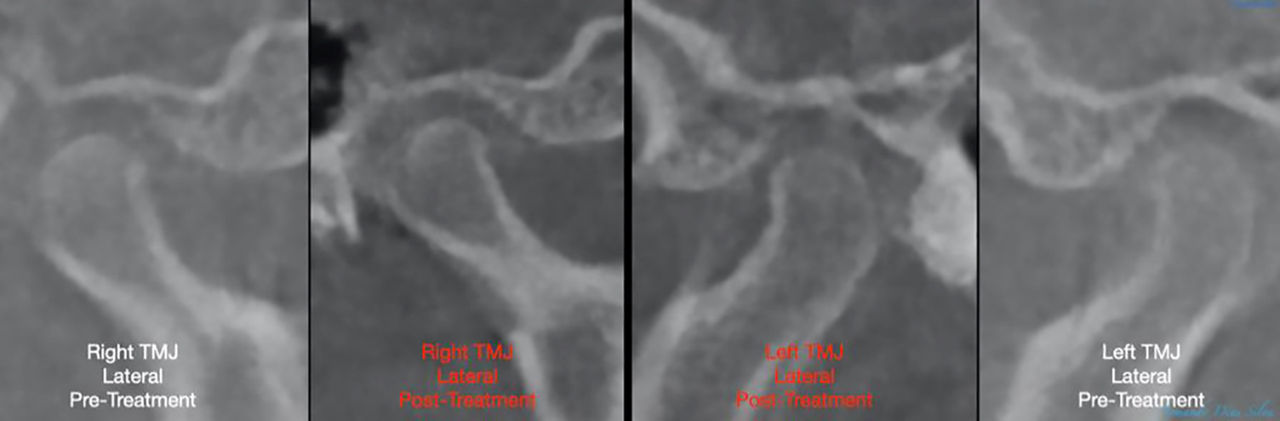

• Sin cambios en la posición del cóndilo

Sin cambios en la posición del cóndilo